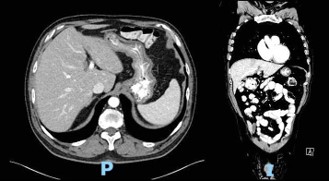

Computed Tomography (CT) scan performed at the time of admission revealed abundant food content with organized appearance in the abdomen (Figure 1), which was morphologically similar to that observed in previous CT scans. The findings supported chronic food retention with difficulty in gastric emptying at the level of pyloric antrum. Pharyngo-esophageal study revealed the presence of a bezoar occupying the entire gastric chamber with normal esophageal motility (Figure 2).

The patient followed an excellent clinical course, with full resolution of the symptoms after three months of treatment. The follow-up CT scan obtained three months (Figure 3) and six months (Figure 4) after admission revealed the complete dissolution of the bezoar. Annual clinical follow-up was performed until June 2025, with no recurrence of symptoms of bezoar reformation.